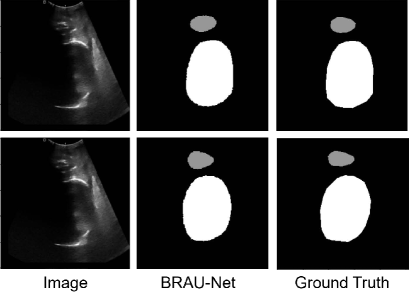

The BRAU-Net is implemented based on Python 3.7 and PyTorch 1.13.1. All our experiments were conducted on a single NVIDIA GeForce RTX 3060Ti with 8GB. We employed the Adam optimizer optimize our model during the back propagation. The data augmentations such as flips, rotations are used to enhance the diversity of the data. The number of attention heads and topks in each stage are 2, 4, 8, 16 and 4, 8, 16, -2, respectively. We set C to 96 and e to 3, respectively. The BRAU-Net is trained from scratch. Since the test set was not previously published, we randomly split the 4000 cases into separate training(3600 cases) and validation(400 cases) datasets. And the average Dice-Similarity coefficient (DSC) and average Hausdorff Distance(HD) are used as evaluation metric to evaluate our method. The quantitative results for the validation dataset(400cases) are presented in Table 1. We also demonstrate visualization results in Figure 3.